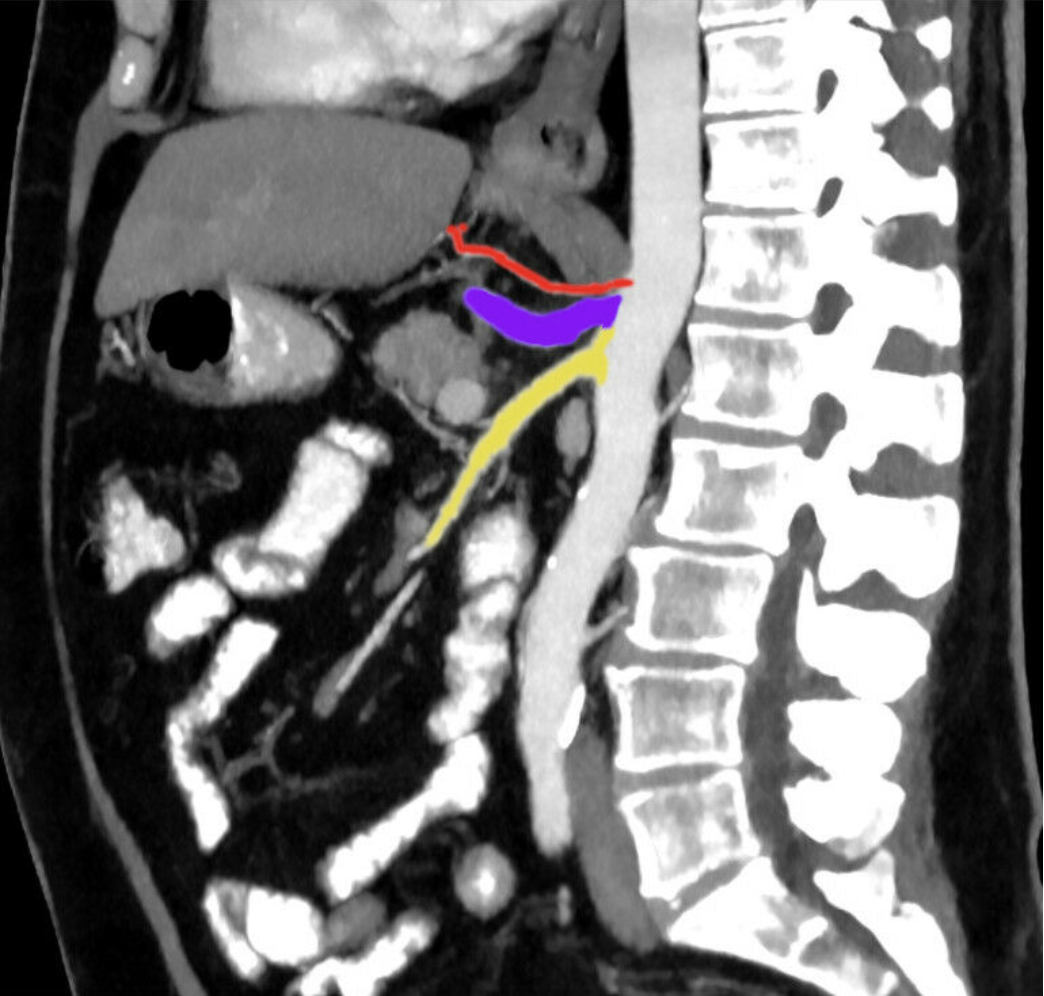

2.65 Die Abbildung zeigt einen CT-Schnitt der arteriellen Gefäße nach Kontrastmittelgabe.

Welche Arterie ist in der Abbildung rot markiert?

- (A) A. gastrica sinistra

- (B) A. hepatica communis

- (C) A. lienalis

- (D) A. mesenterica superior

- (E) A. gastroduodenalis